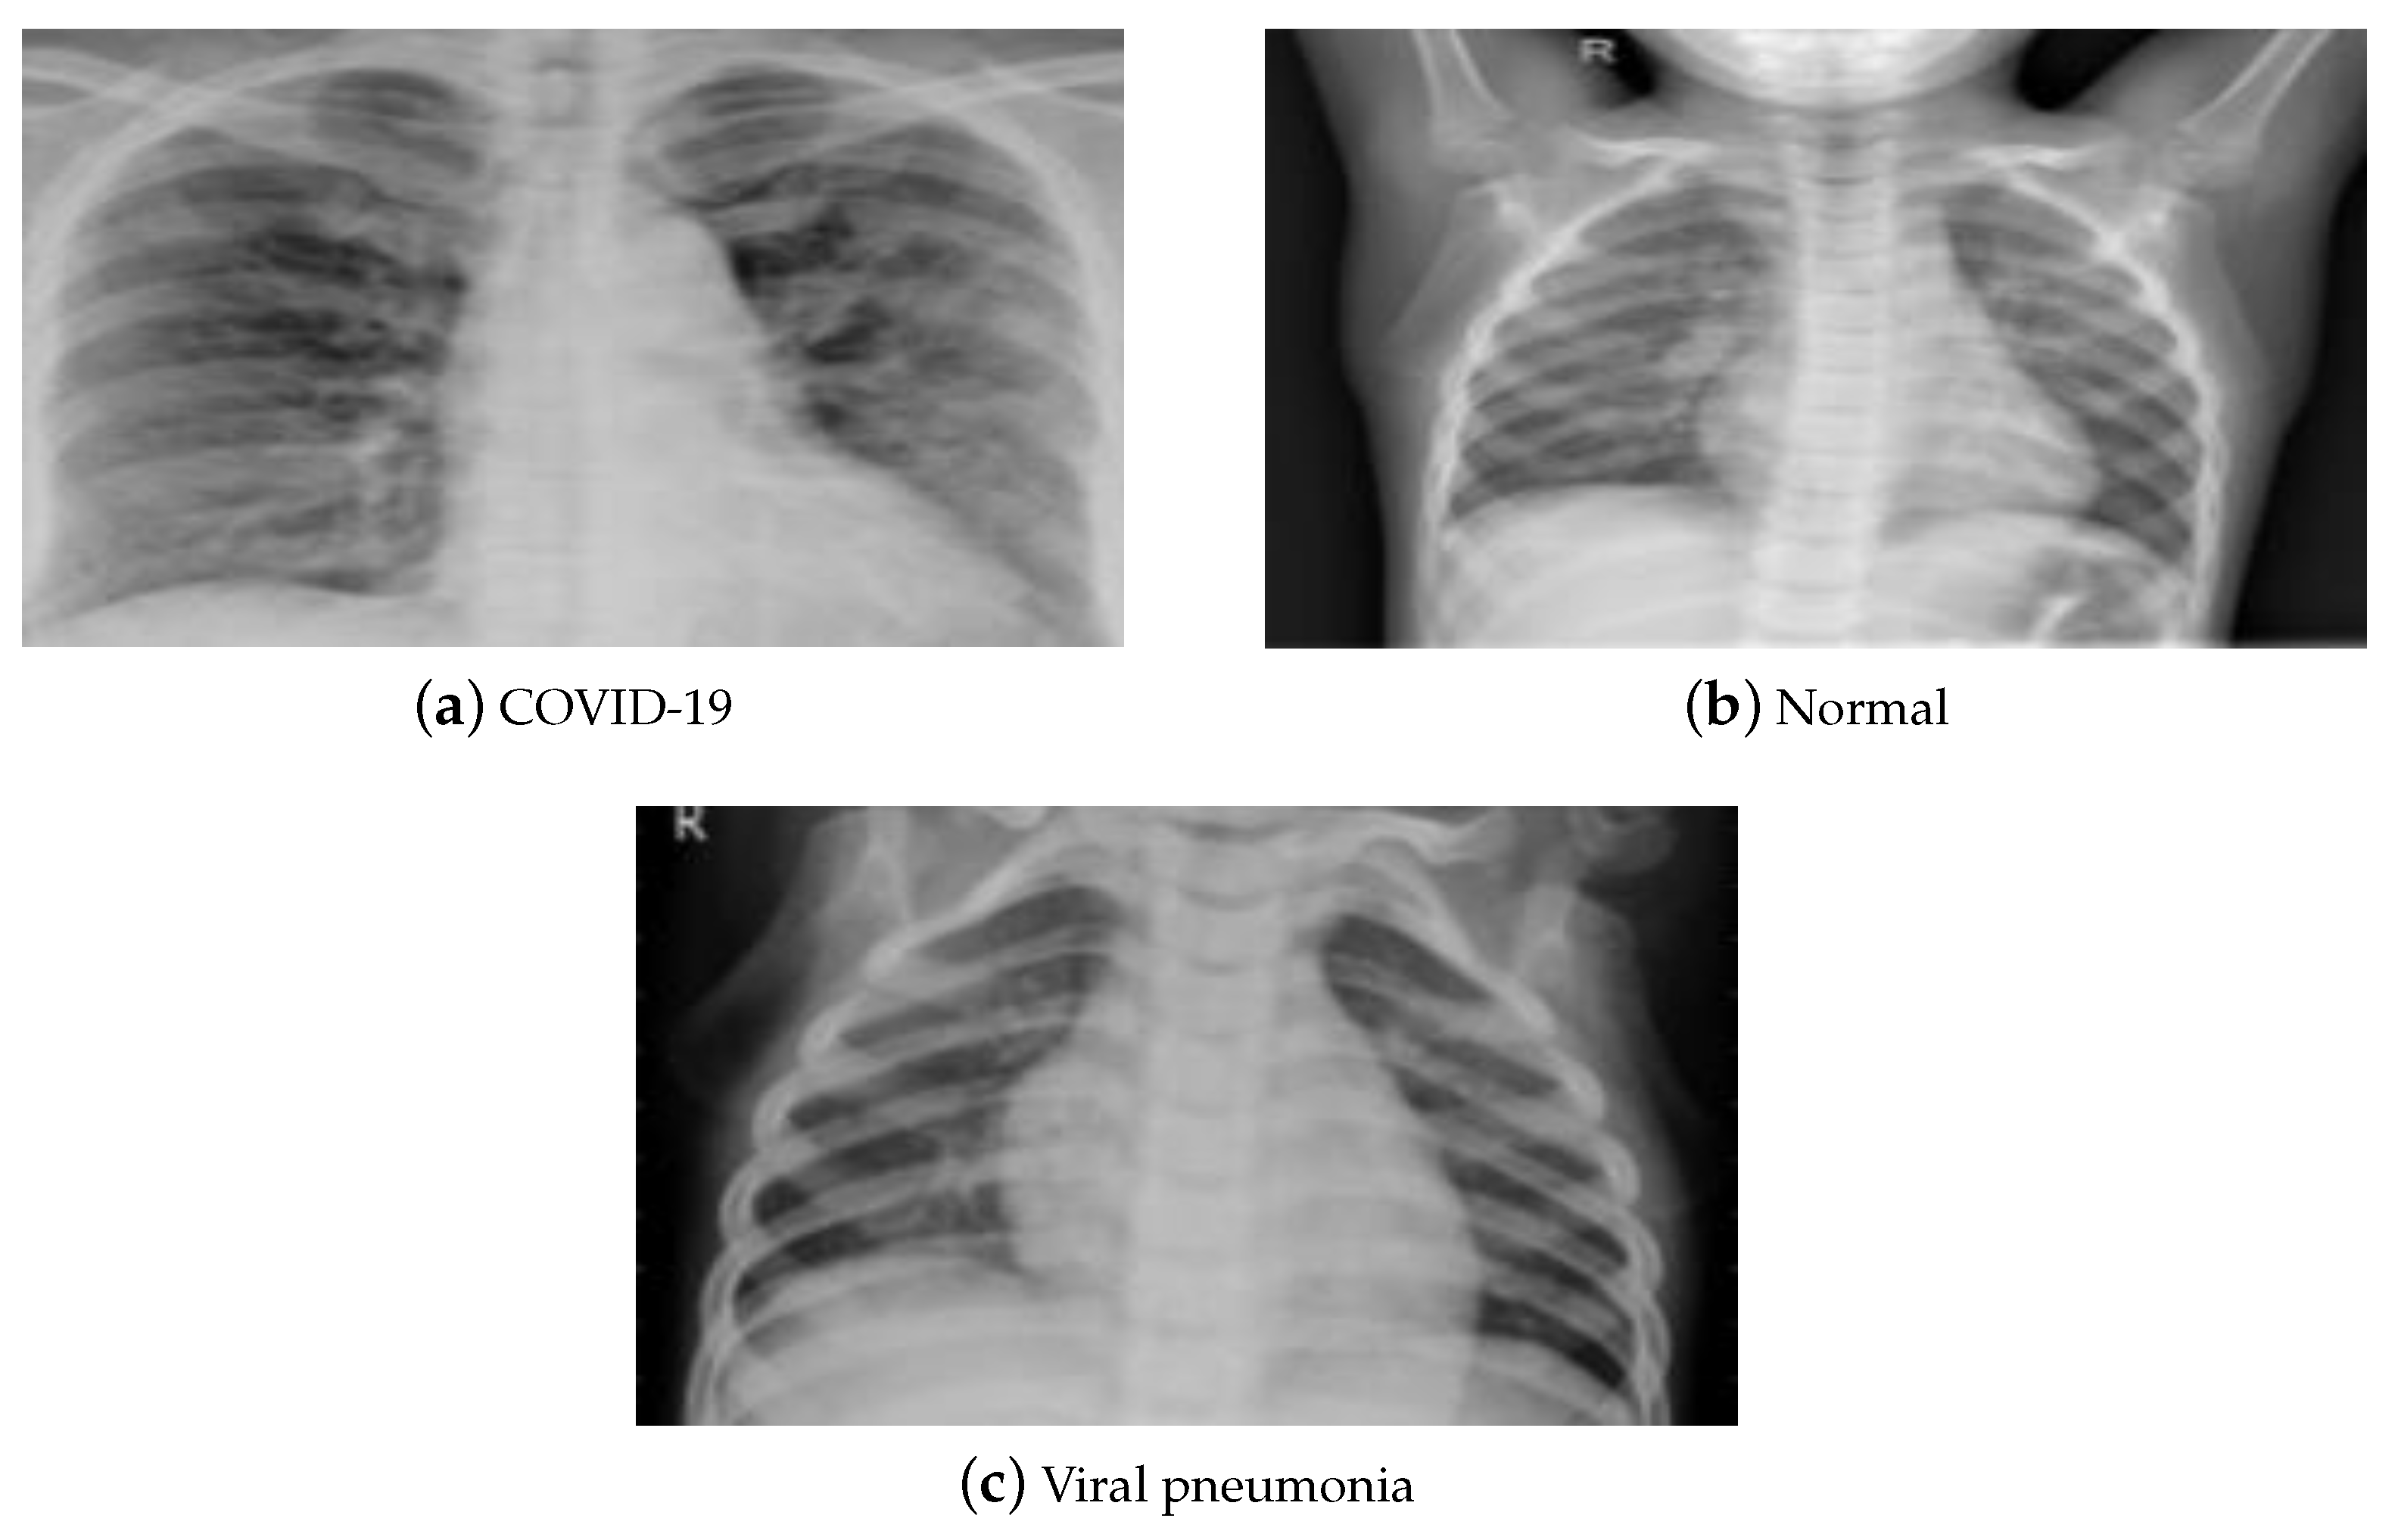

X-rays and CT are two typical medical imaging modalities used to diagnose and assess the severity of a disease. Each medical imaging technique has its pros and cons. Due to its low cost and considerable availability worldwide, X-ray imaging is the most commonly utilized medical imaging approach for COVID-19 diagnosis. It is processed using elementary techniques, which decreases imaging time and hence the risk of viral propagation. Compared to a CT scan, X-ray imaging is non-invasive and generates minimal radiation exposure. Despite its benefits, X-rays are less sensitive, which may result in a mistaken diagnosis of the illness with early and moderate symptoms. CT scans, on the other hand, are more sensitive and provide precise information about the damaged location, resulting in reliable judgment. Therefore, CT scans are crucial in the diagnosis of lung disorders, and hence are more reliable regarding the early detection of COVID-19. However, its expensive cost, increased radiation dosage, and resource restrictions bound its usage. This paper utilized the publicly accessible pneumonia normal-chest-X-ray posteroanterior (pa) data set [52]. It consists of images gathered from the websites of the Italian Society of Radiology (SIRM), Kaggle, Radiopedia, and Figshare data repository. The data set contains posteroanterior (PA) chest X-ray images divided into three classes (COVID-19, pneumonia, and normal). It consists of 2313 samples for each class, resulting in 6939 samples. Figure 4 displays a sample of that data set.

Figure 4.

(a–c) X-ray data set samples [52].